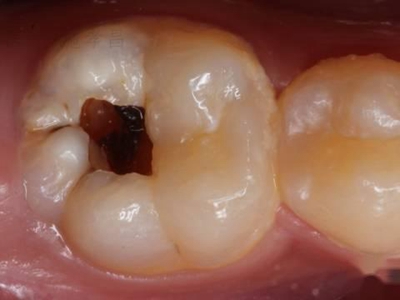

年轻恒牙龋指的是儿童萌出不久的第一恒磨牙龋病和上颌恒切牙龋病,其中第一恒磨牙龋病占年轻恒牙龋的90%,发病早,进展快,可表现为白垩色斑片、点隙窝沟墨浸状龋坏或龋洞。本病的发生和年轻恒牙的特点以及儿童饮食、口腔卫生等因素有关。

年轻恒牙龋好发于第一、二恒磨牙(牙合)面、邻面,上颌中切牙邻面,多为急性龋,龋坏进展快。平滑面的早期龋多为白垩色的斑片,点隙窝沟的早期龋多为浸墨状,表面粗糙。如果早期龋不及时治疗,可逐渐形成大而深的龋洞,易导致牙髓炎和根尖周炎。